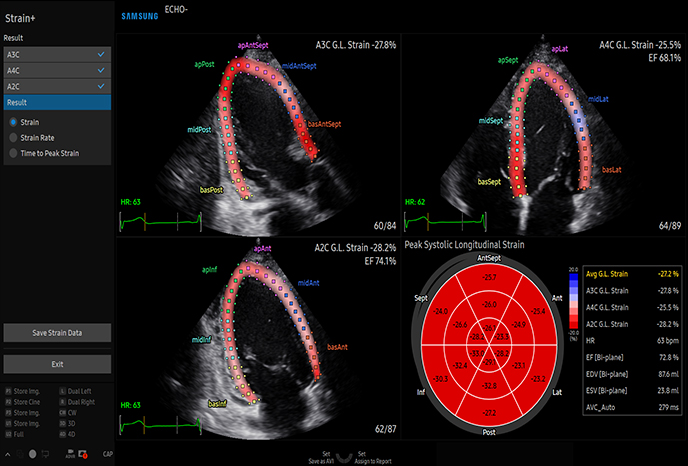

하이앤드 초음파 장비를

활용한 정밀 심장 검사

심장 질환 진단에서 가장 중요한 것은 ‘심장의 상태를 얼마나 정확하게 볼 수 있느냐’입니다. 저희 센터는 대학병원급 하이앤드 초음파 장비를 도입하여, 실시간 3D 렌더링으로 정밀 진단이 가능하며, 심장의 구조·혈류·기능을 실시간 고해상도로 관찰합니다.

미세한 판막 움직임, 혈류 속도 변화, 심방·심실 크기와 수축력까지 정밀하게 분석할 수 있어, 심장질환의 조기 발견과 치료 계획 수립에 큰 차이를 만듭니다.